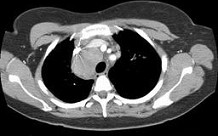

- 单项选择题女,33岁, 咳嗽,乏力, 低热,皮肤有结节, 结合CT图像,最可能的诊断是 ( )

D、结节病